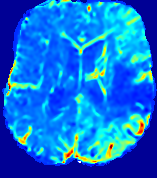

LesionRefer to captionRefer to captionRefer to captionRefer to captionRefer to captionRefer to caption𝐕rgbsubscript𝐕𝑟𝑔𝑏{\bf{V}}_{rgb}Refer to captionRefer to captionRefer to captionRefer to captionRefer to captionRefer to caption𝐕2subscriptnorm𝐕2{\|\bf{V}}\|_{2}Refer to captionRefer to captionRefer to captionRefer to captionRefer to captionRefer to captionRefer to caption3.53.53.52.82.82.82.12.12.11.41.41.40.70.70.70.00.00.0(mm/s)𝑚𝑚𝑠(mm/s)D𝐷DRefer to captionRefer to captionRefer to captionRefer to captionRefer to captionRefer to captionRefer to caption0.0200.0200.0200.0160.0160.0160.0120.0120.0120.0080.0080.0080.0040.0040.0040.0000.0000.000(mm2/s)𝑚superscript𝑚2𝑠(mm^{2}/s)Slice #1Slice #2Slice #3Slice #4Slice #5Slice #6

Figure 3: PIANO feature maps for one stroke patient, where the lesion is located in the left hemisphere. Top row: segmented stroke lesion region (white) on different slices, obtained from ISLES 2017. The corresponding slices for the PIANO feature maps are shown in the following rows.

For a better insight into an estimated velocity field 𝐕𝐕{\bf{V}} and diffusion field 𝐃𝐃{\bf{D}}, we compute the following maps: (1) 𝐕rgbsubscript𝐕𝑟𝑔𝑏{\bf{V}}_{rgb}: Color-coded orientation map of 𝐕=(Vx,Vy,Vz)T𝐕superscriptsuperscript𝑉𝑥superscript𝑉𝑦superscript𝑉𝑧𝑇{\bf{V}}=(V^{x},V^{y},V^{z})^{T}, obtained by normalizing 𝐕𝐕{\bf{V}} to unit length and mapping its 3 components to red, green, blue respectively; (2) 𝐕2subscriptnorm𝐕2\|{\bf{V}}\|_{2}: 222 norm of 𝐕𝐕{\bf{V}}; (3) D𝐷D: scalar field in Eq. 5.

Fig. 3 and Fig. 4 show the PIANO feature maps estimated from two ISLES 2017 patients: all are highly consistent with the lesion in both cases. Details of the blood flow trajectories are revealed in 𝐕rgbsubscript𝐕𝑟𝑔𝑏{\bf{V}}_{rgb} by the ridged patterns and the sharp changes of colors in the unaffected (right) hemisphere, while the flat patterns appearing within the lesion provide little directional information about the velocity and indicate low velocity magnitudes. Velocity magnitudes are more directly visualized via 𝐕2subscriptnorm𝐕2\|{\bf{V}}\|_{2}, from which one can easily locate the lesion where 𝐕2subscriptnorm𝐕2\|{\bf{V}}\|_{2} is low. D𝐷D also indicates lower diffusion values in the lesion, though with less contrast potentially due to the fact that it captures the accumulated effect of CA diffusion at the voxel-level.